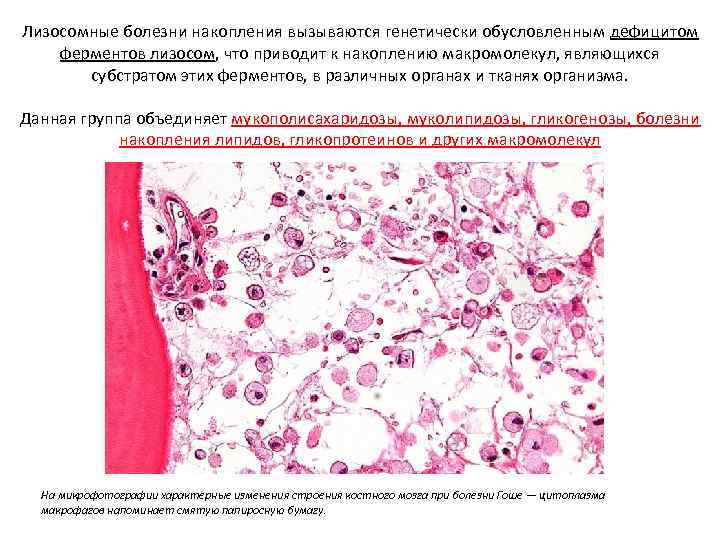

Лизосомные болезни накопления вызываются генетически обусловленным дефицитом ферментов лизосом, что приводит к накоплению макромолекул, являющихся субстратом этих ферментов, в различных органах и тканях организма. Данная группа объединяет мукополисахаридозы, муколипидозы, гликогенозы, болезни накопления липидов, гликопротеинов и других макромолекул На микрофотографии характерные изменения строения костного мозга при болезни Гоше — цитоплазма макрофагов напоминает смятую папиросную бумагу.